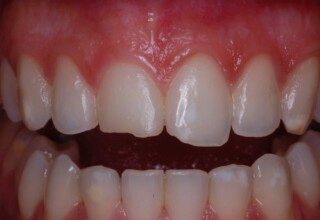

Restoration of bilateral diastemas between central and lateral incisors.

Diastemas were created mainly because of narrow laterals. After orthodontic treatment was finalized, the diastemas were closed with two composite resin restorations.